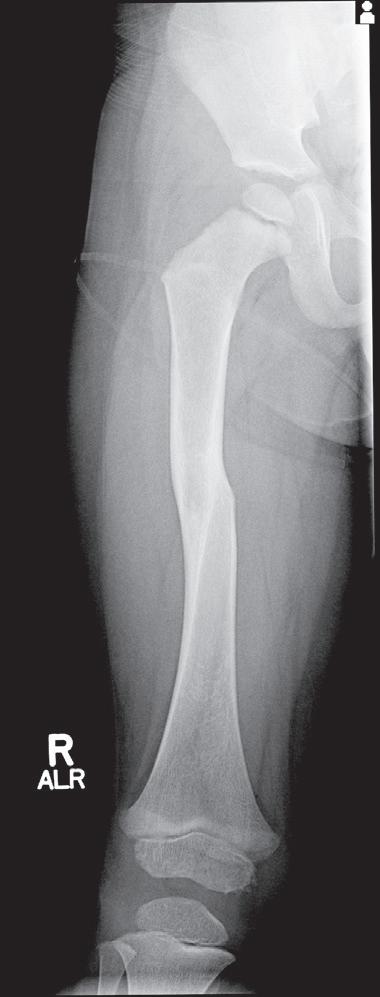

Pediatric bony injuries are more often treated by closed reduction than by open reduction because of the short time to union and the ease of obtaining and maintaining near-anatomic reductions, as well as the potential for remodeling (Fig. 1.8). The quality of anesthesia/analgesia provided to the child is strongly correlated with the quality of the reduction.22

Fig. 1.8 (A) Anteroposterior and lateral radiographs of a 15-year-old boy who sustained a displaced transverse fracture of the diaphysis of his tibia. (B) Follow-up at 4 months shows abundant periosteal healing, although a portion of the fracture line is still evident. It is characteristic for pediatric long bone fractures to heal early with periosteal callus; secondarily, the diaphyseal cortex heals and remodels.